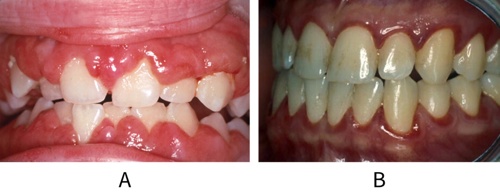

Gingival enlargement, inflammation and bleeding can be a sign of an underlying medical condition that requires investigation, such as undiagnosed leukaemia, in both children and adults (see figure: Leukaemia).

Image A shows gingival enlargement as a result of acute myeloid leukaemia. Image B shows marginal gingivitis, due to neutropenia, in a leukaemia patient awaiting bone marrow transplant. The patient had scrupulous oral hygiene.

In cases of unexplained gingivitis or gingival enlargement which does not respond to treatment as expected, or the extent of the condition is inconsistent with the level of oral hygiene observed, consider urgent referral to an oral medicine specialist or specialist periodontist.